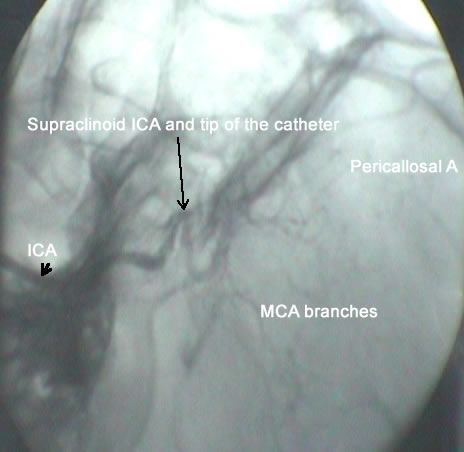

Exposure of the right CCA, ECA with the branches arising from the last. The right hypoglossal nerve was dissected and preserved. There was a huge lymphnode in the area which was resected to obtain visual control in the field. The ICA was followed from distal to proximal to be sure that no abnormality could be present at the bifurcation. The right ICA is hypoplastic and its external diameter less than 3 mm. Direct angiography done demonstrating that the ICA is completely occluded 10 mm above the bifurcation and no pulsation is noted. After clamping of the right CCA and ECA arteriotomy was done. There was an atheroma completely occluding the right ICA. It was removed but no back flow was obtained. Using subclavian catheter No 20 three way with the brown canula connected to the end of the catheter, gradual dilatation and cleaning with saline and heparin was applied. Using the C-arm, the tip of the catheter was followed and continuous angiography and cleaning was performed until the right ophthalmic artery was seen. The segment above this level up to the bifurcation of ICA to A1 and M1 which usually 3-5 mm in length required 20 min and 10 passes to clean and dilate the area until proper angiography of the right circulation was established. The canula was removed and there was back flow from the ICA. Using Dacron patch the arteriotomy site was closed and control hemostasis was achieved after removing the clamps. The hypoplastic ICA regained good pulsation after that. Routine closure.

The circulation restored after long effort.